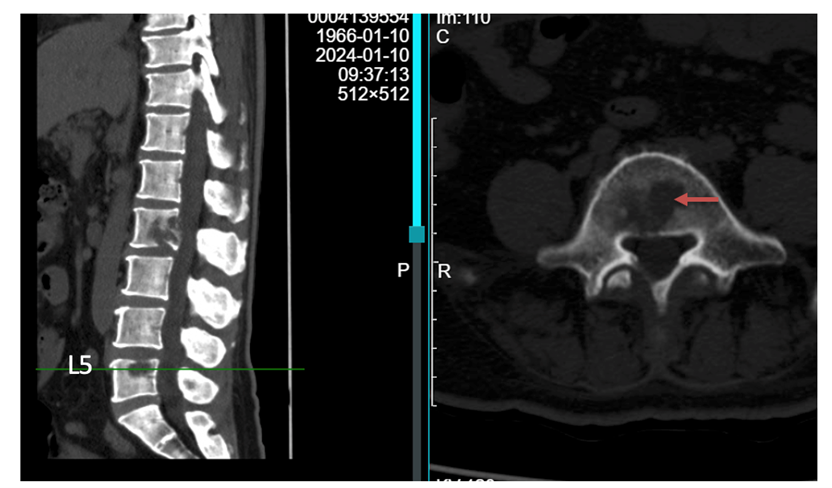

读片:CT及MRI检查提示,T2,L2,L5椎体骨质破坏,红色箭头所指为转移病灶所在位置,可见L2椎体病灶已侵犯后壁,突入椎管内。

患者为胸腰椎多节段的转移,且椎体病灶位置多位于后方,后壁已破损(T2,L2),因此不宜行椎体成形术(存在骨水泥渗漏至椎管风险)。

术后6月与术前CT对比,红色圆圈处可见术后6月,椎体后壁有明显骨化形成,黄色箭头处可见术后6月,非消融侧病灶亦有明显缩小